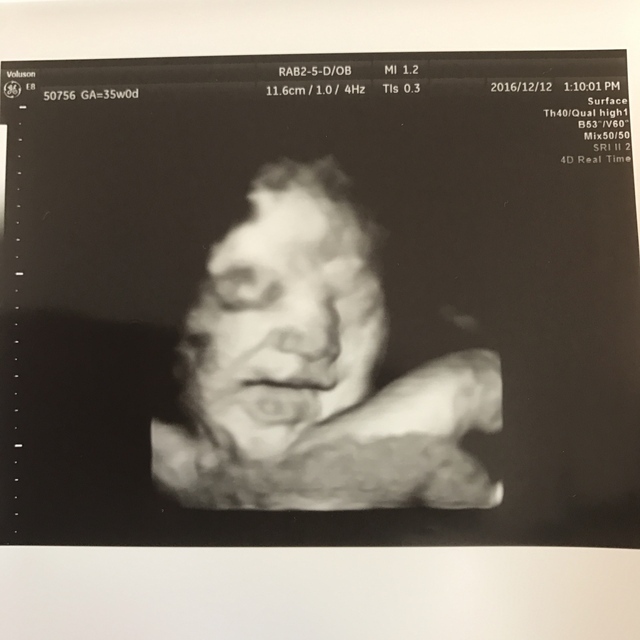

35週0日(35w0d・男の子)|infinitent さん(31歳)

エコー写真撮影時のエピソード:

基本は3Dでの撮影でしたが、この日は4Dでの撮影で胎児の表情や手や足がよくわかるもので、お腹の中で胎児が元気に育ってくれている事がよくわかり感動しました。

この時、お顔も隠れずに上手に撮らせてくれて、笑ってもいてかわいかったのを覚えています。 早産で出産したのでこの5日後に生まれたと思うとびっくりです。